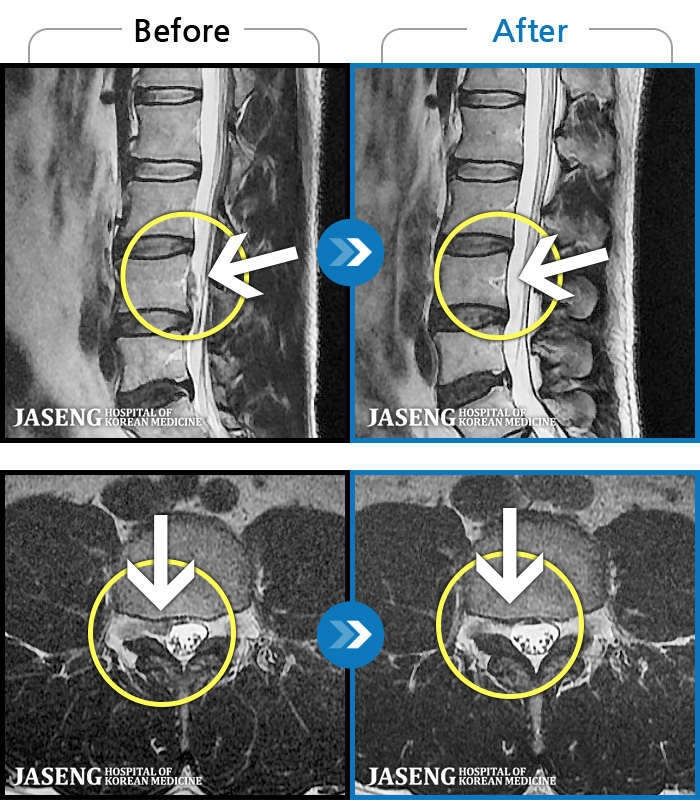

MRI 치료사례

환자에게 사전 동의를 받아 동일 조건에서 촬영되었습니다.

허리디스크

허리통증이 심해서 숙이기 어렵고 차에서 내리기 힘들었습니다.